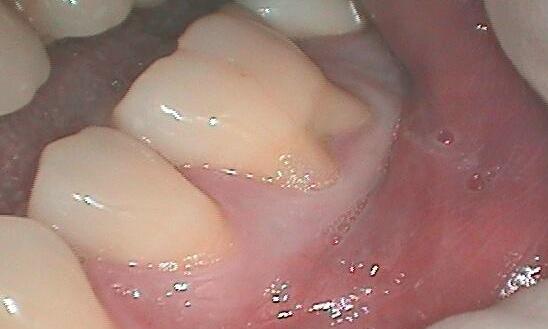

Sometimes trauma or injury caused by brushing too hard can cause permanent damage to the gums and cause them to recede. However, bacteria often cause the build-up of plaque under the gums. Plaque pushes the gums away from the tooth, breaking the seal the gums should form around it, inflaming it, and eventually causing it to recede.

The first stage of this process is called gingivitis and is fully reversible. However, after that, the damage the plaque and tartar do to the gums cannot be reversed, but it can still be managed and prevented from causing even more damage.

In some cases, if caught early enough, a simple minor gum recession repair surgery is all that is needed to correct the gums and restore that protection to the tooth.